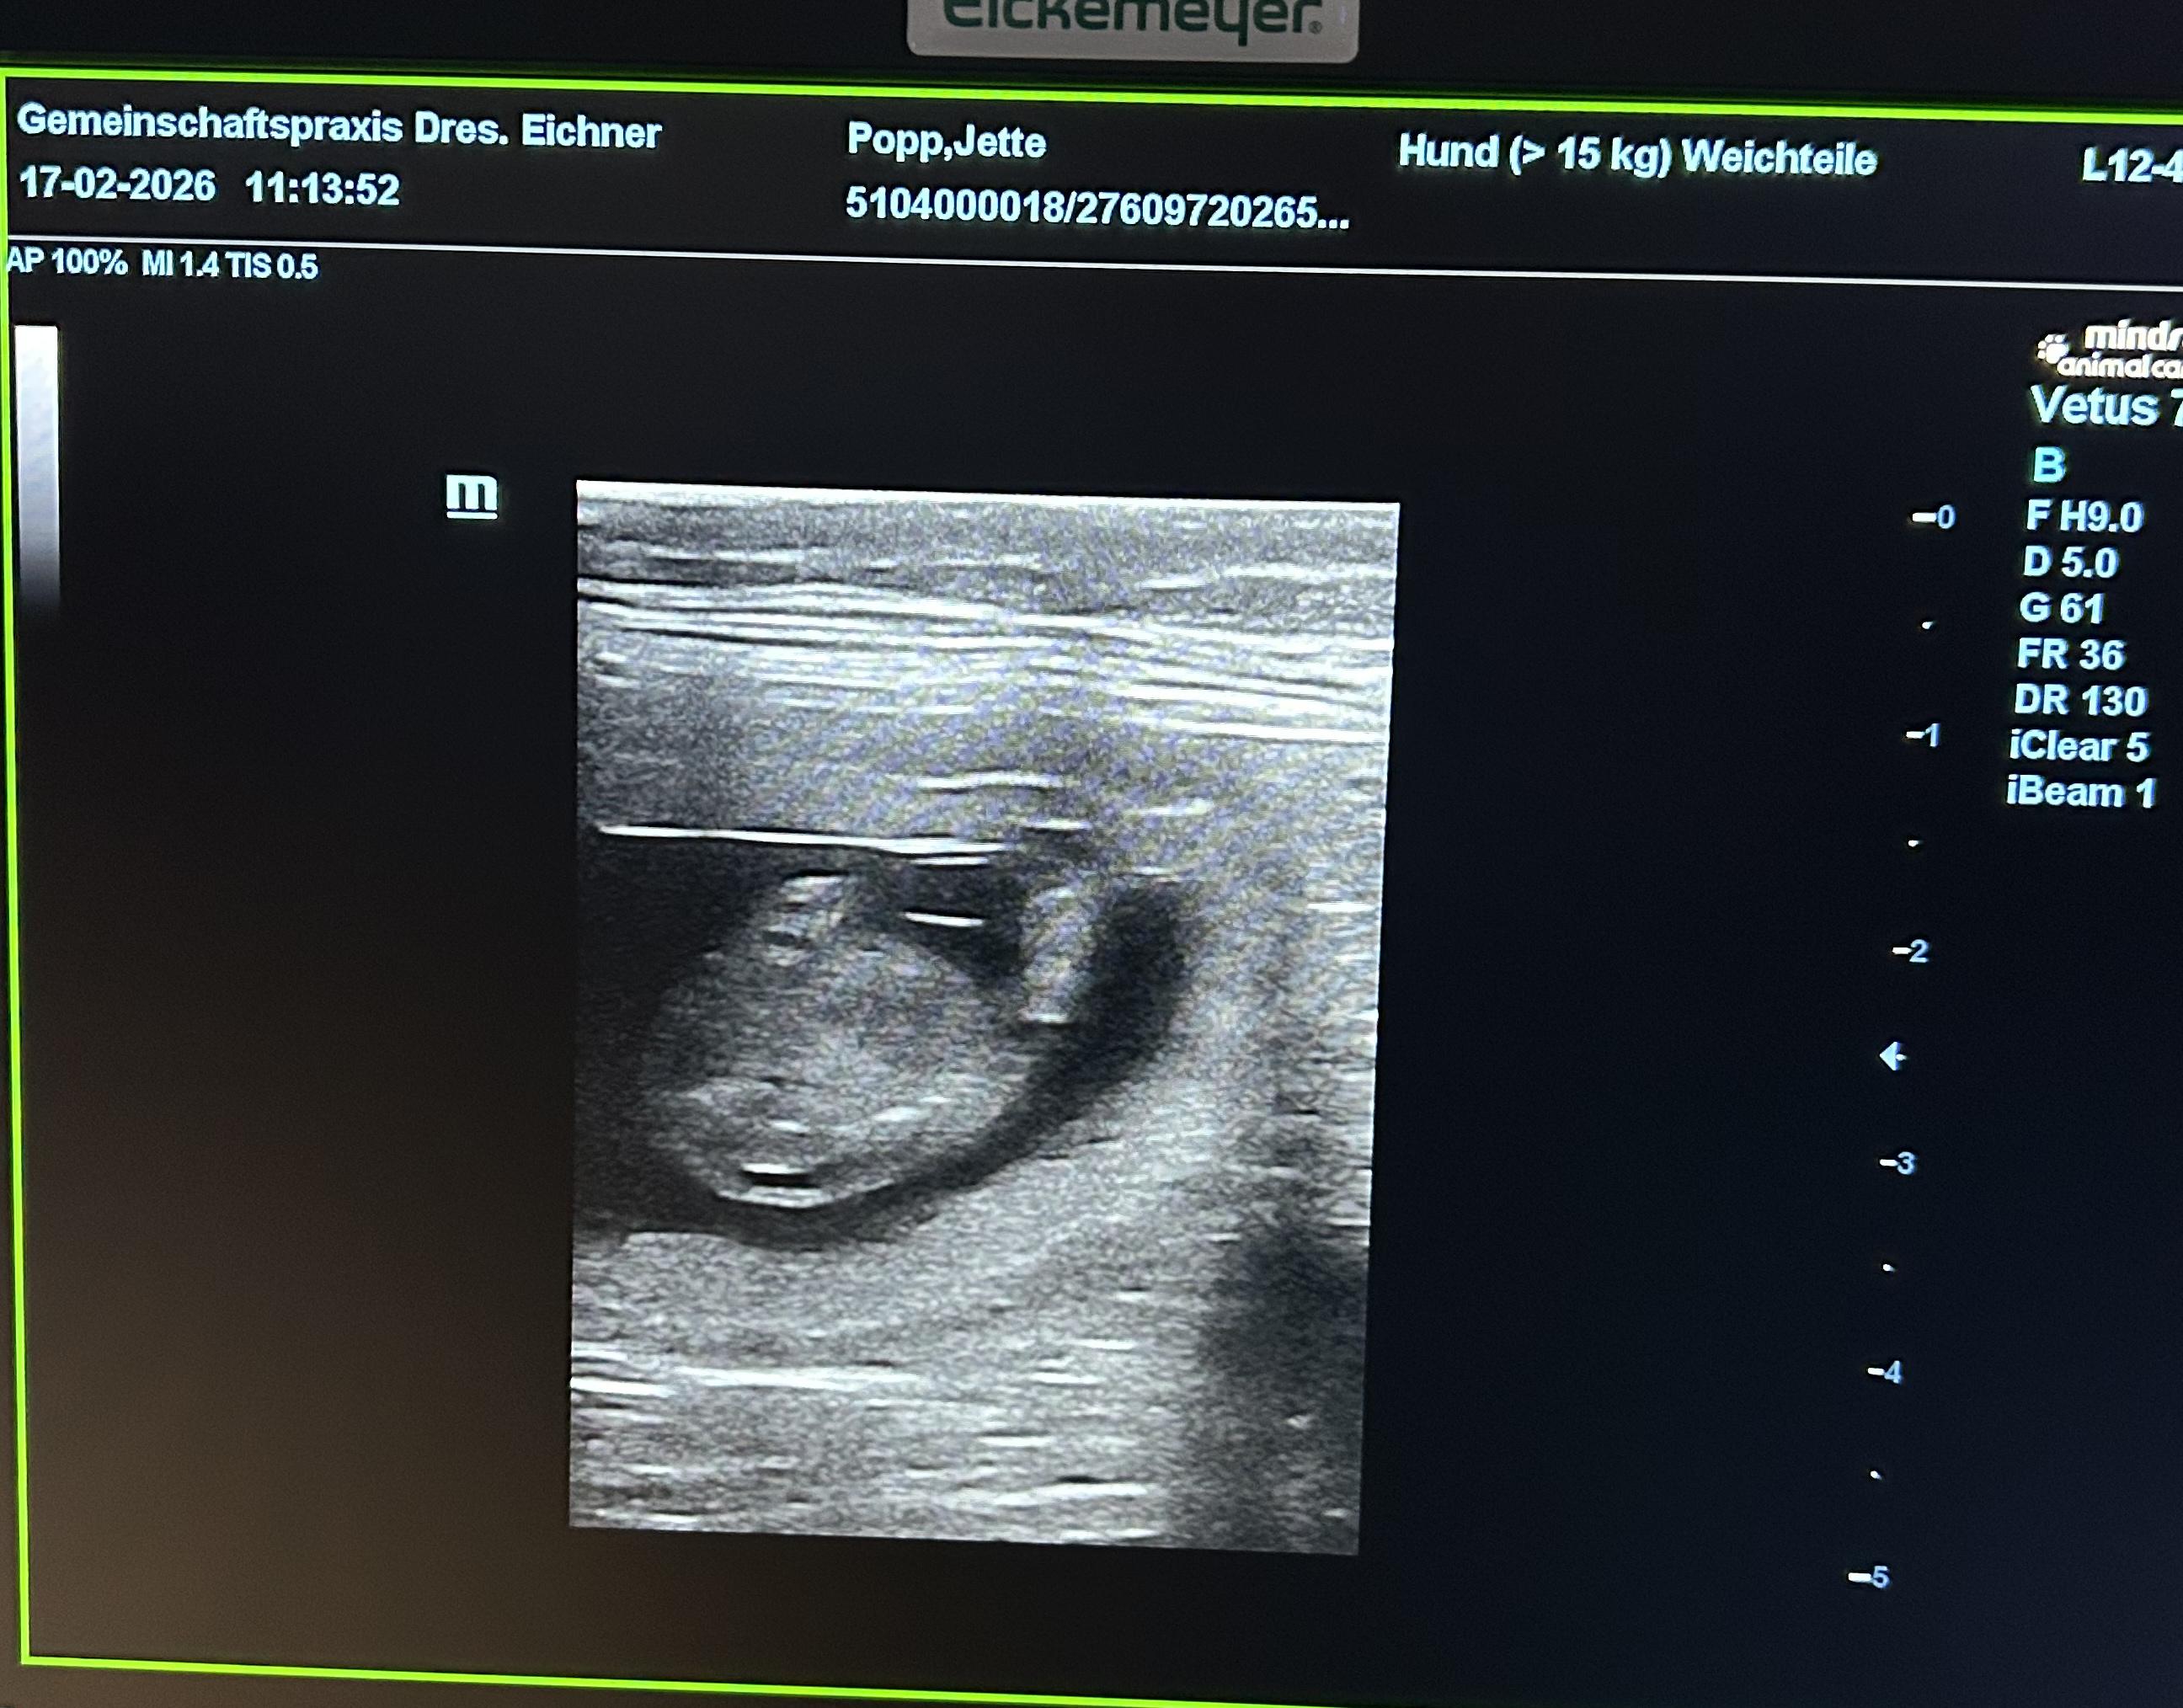

Jette hat 3 starke Jungs geboren